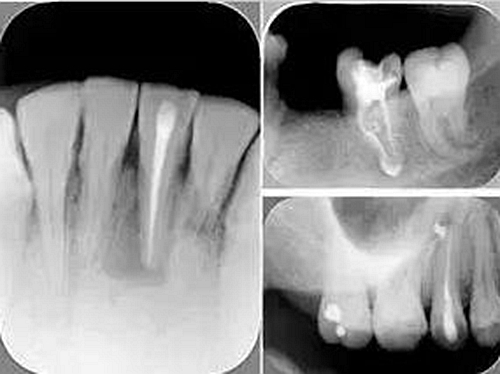

三、開髓孔

1. 正常開髓孔的位置和大小

左圖為正常開髓孔的大小和位置。左邊圖為下顎,右邊圖為上顎。

2. 根管治療中開髓孔的設(shè)計(jì)標(biāo)準(zhǔn)

根管治療需去除髓腔內(nèi)容物(去除髓室頂),建立所有根管的入路,允許沖洗液大量沖洗。開髓孔的設(shè)計(jì)標(biāo)準(zhǔn)以建立通路為目的,從而建立良好的視野和術(shù)野。

( 1 )直線通路:根管治療時(shí)需要一個(gè)直線通路,直線通路能夠達(dá)到根尖三分之一

測(cè)量標(biāo)準(zhǔn):以允許根管器械直線并直接進(jìn)入根尖 1/3 且不接觸冠方各壁為標(biāo)準(zhǔn)。

( 2 )髓腔其他改變:如髓室頂、繼發(fā)性牙本質(zhì)、修復(fù)性或增齡性牙本質(zhì)。見左圖。

右圖中有繼發(fā)性牙本質(zhì),切削后獲得直線通路。